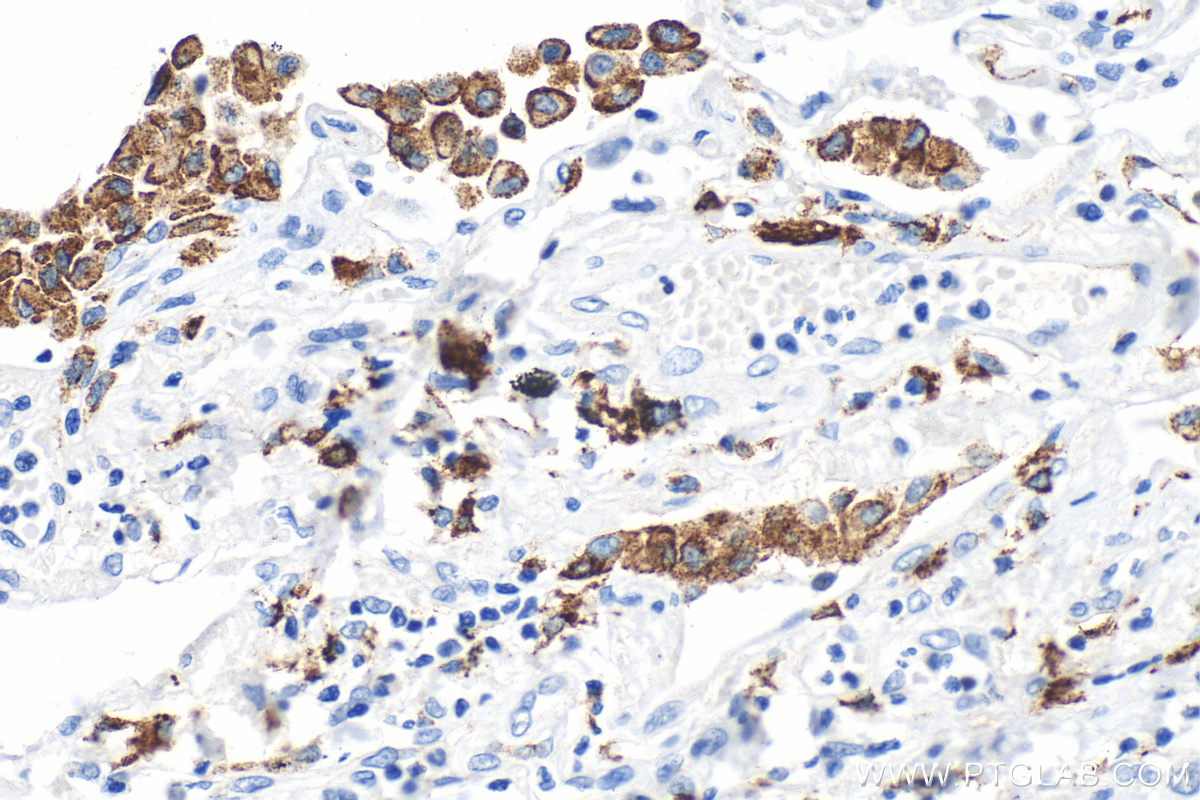

IHC staining of human lung cancer using 81525-1-RR (same clone as 81525-1-PBS)

Immunohistochemical analysis of paraffin-embedded human lung cancer tissue slide using 81525-1-RR (CD206 antibody) at dilution of 1:2000 (under 40x lens). Heat mediated antigen retrieval with Tris-EDTA buffer (pH 9.0). This data was developed using the same antibody clone with 81525-1-PBS in a different storage buffer formulation.